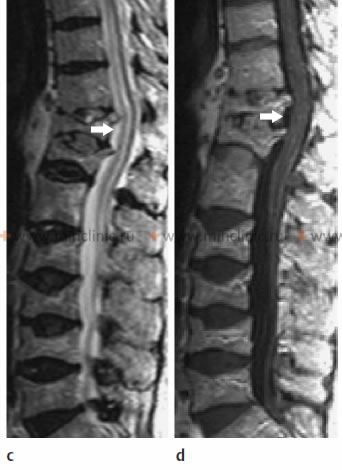

ხერხემლის მაგნიტურ-რეზონანსულ ტომოგრაფიაზე ჩანს კომპრესიული მოტეხილობის შედეგად მიღებული ზურგის ტვინის მწვავე იშემია მალების სხეულების გადაადგილების თანხლებით გამოხატული ოსტეოპოროზის დროს.